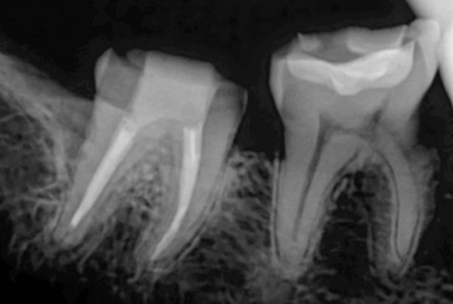

위 사진들은 현직 치과의사들이

저희 웃는얼굴 치과에서 치료 받은 실제 사례들입니다.

비 전문가 눈에는 그냥 흔한 엑스레이 사진일 뿐이겠지만

치과의사들이라면 알아챕니다.

저 치료가 얼마나 난이도 있는 치료였는지,

얼마나 정성이 들어갔는지를 말이지요.